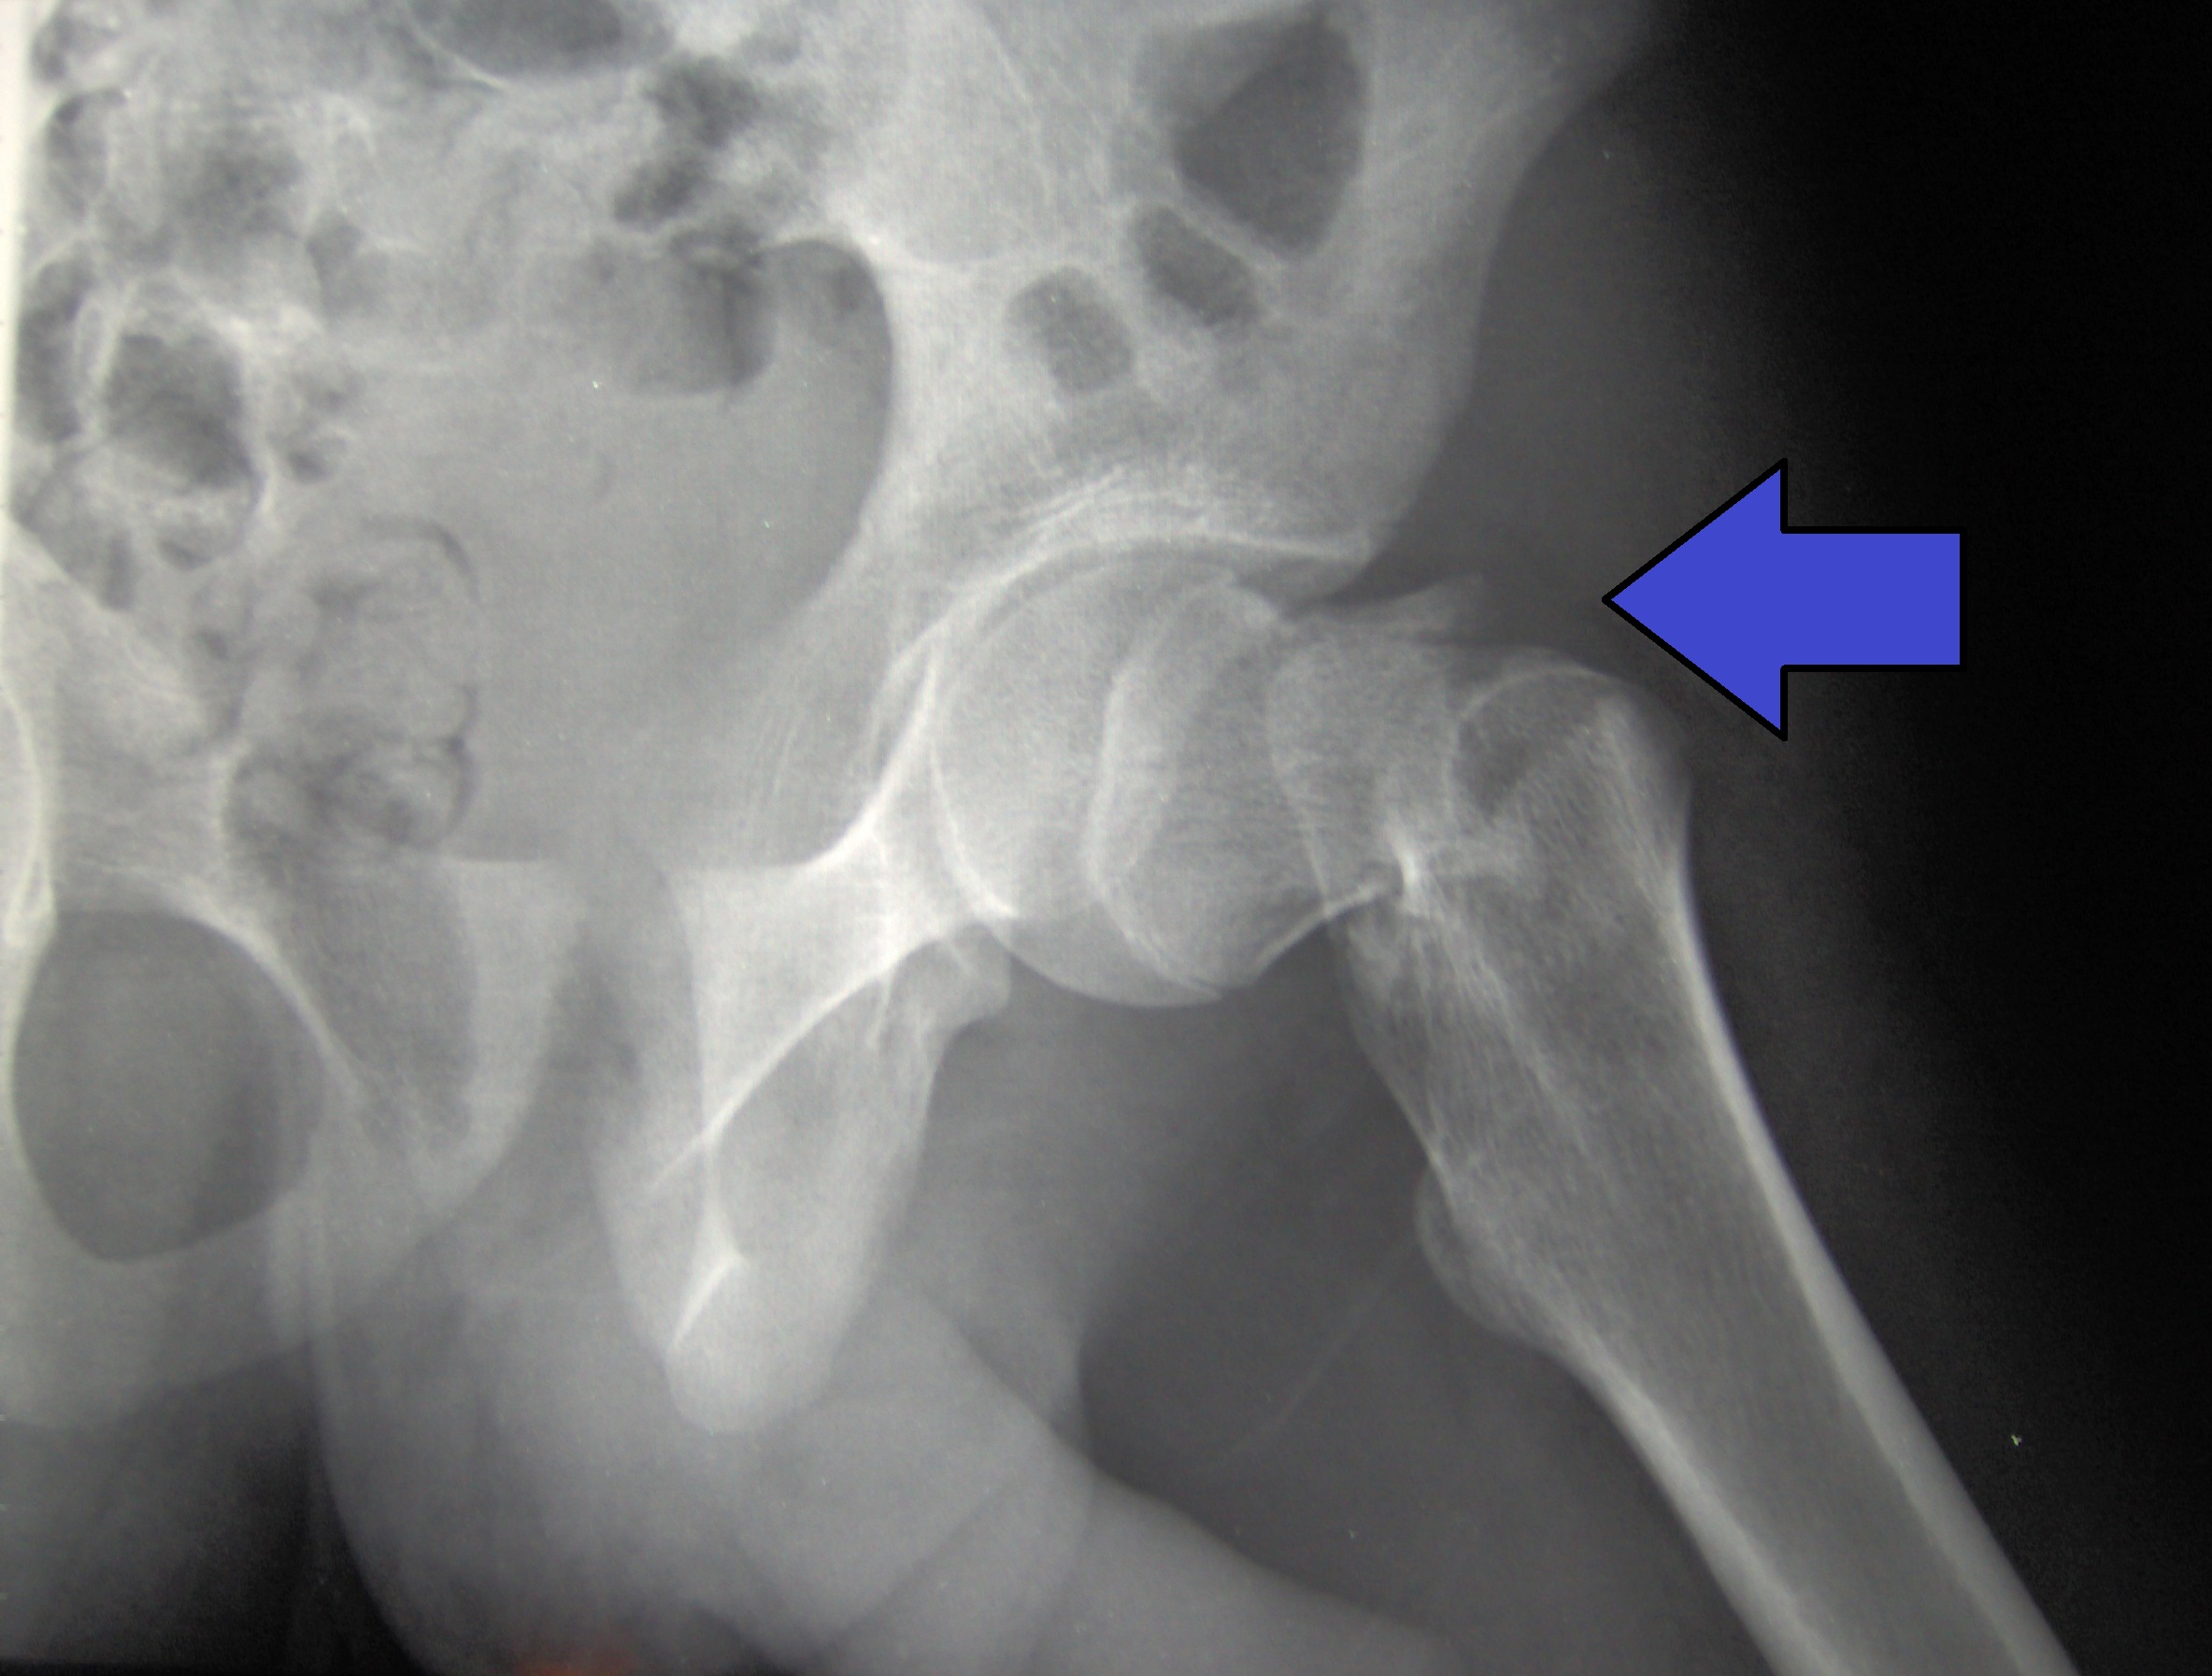

Osteoporosis inducida por glucocorticoides: conceptos novedosos e implicaciones clínicas.

01 octubre 2025

Esta revisión destaca cómo el microambiente óseo responde a concentraciones suprafisiológicas de glucocorticoides y analiza las bases de la fragilidad esquelética y las fracturas. Revisa el uso y las limitaciones de las tecnologías de imagen y las herramientas de predicción actuales y emergentes, y analiza las estrategias de tratamiento osteoformador y antirresortivo, así como su uso para prevenir y tratar la osteoporosis inducida por glucocorticoides. Lancet Diabetes Endocrinol, 26 de septiembre de 2025